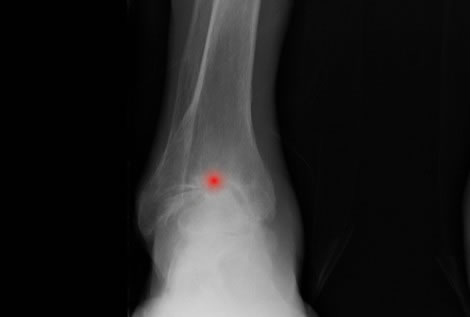

El tobillo es la articulación que conecta la pierna con el pie. En ella se relacionan tres huesos: tibia, peroné y astrágalo. Esta estructura ósea está fuertemente reforzada por músculos, tendones y potentes ligamentos que la estabilizan.